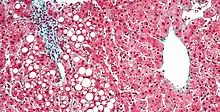

| Micrograph showing a fatty liver (macrovesicular steatosis), as seen in non-alcoholic fatty liver disease. Trichrome stain. | |

Pathology

The fatty change represents the intracytoplasmatic accumulation of triglycerides (neutral fats). At the beginning, the hepatocytes present small fat vacuoles (liposomes) around the nucleus (microvesicular fatty change). In this stage, liver cells are filled with multiple fat droplets that do not displace the centrally located nucleus. In the late stages, the size of the vacuoles increases, pushing the nucleus to the periphery of the cell, giving a characteristic signet ring appearance (macrovesicular fatty change). These vesicles are well-delineated and optically "empty" because fats dissolve during tissue processing. Large vacuoles may coalesce and produce fatty cysts, which are irreversible lesions. Macrovesicular steatosis is the most common form and is typically associated with alcohol, diabetes, obesity, and corticosteroids. Acute fatty liver of pregnancy and Reye's syndrome are examples of severe liver disease caused by microvesicular fatty change.[19] The diagnosis of steatosis is made when fat in the liver exceeds 5–10% by weight.[13][20][21]